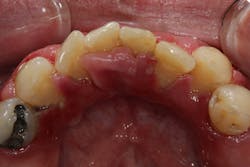

- 50% of the cases are typically attributed to phenytoin (figure 3).

- 10% to 20% of the cases are typically attributed to calcium channel blockers, with nifedipine being the most notable problem (figures 4a and 4b).

Another laser that has been used to treat gingival enlargement and gummy smiles is a 9.3 micron CO2 laser (Solea from Convergent Dental; figure 2a). Unlike other lasers, the Solea laser has the capabilities of removing both soft and hard tissue, precise cutting accuracy due to control of both laser beam power and size, and the ability to cauterize inflamed tissue (figures 4c and 4d). Conventional instrumentation—such as blades, knives, and high-speed burs—can often lead to bleeding after surgical removal when the tissue is inflamed. With this type of CO2 laser, sutures and/or surgical dressing are often not needed.